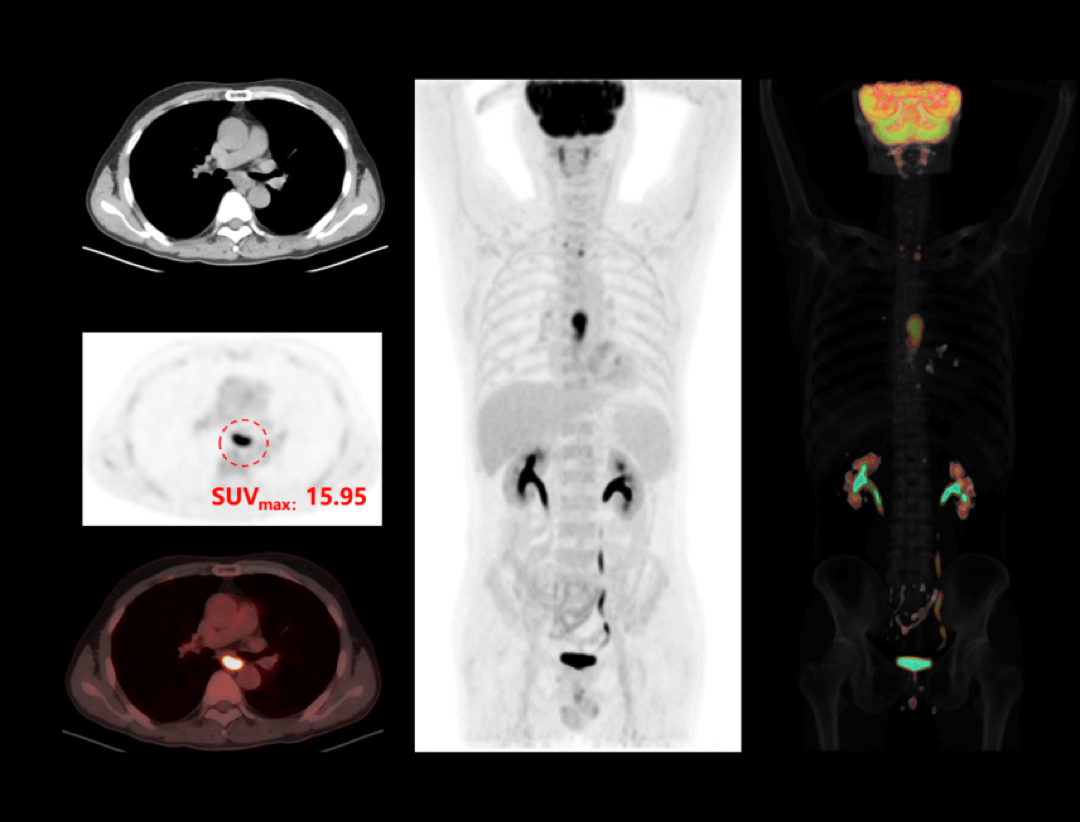

Integrated Oncology Application

The uMI 550 offers a comprehensive solution package for tumor diagnosis and post-therapeutic evaluation on the operation console.